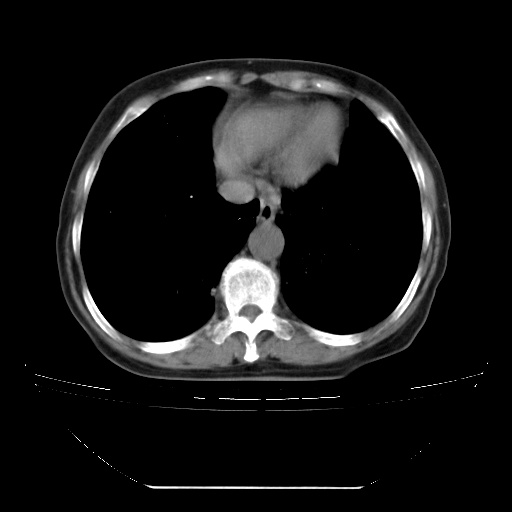

患者女性,72岁,慢性咳嗽3月余,曾抗炎治疗无效果,最近抗结核治疗约半月余,症状缓解。

ct示两肺粟粒状病灶,以两肺上叶尖后段及下叶背段分布为主;首先考虑结核。请战友们分析。

两肺内病灶呈小结节状和树芽状,纵膈的肿大的淋巴结密度不均匀,并见有钙化,考虑为两肺结核可能更大些。

两肺内病灶呈小结节状和树芽状,纵膈的肿大的淋巴结密度不均匀,并见有钙化,多形态病灶,考虑为两肺结核,肝内考虑小囊肿。

考虑两肺播散性肺结核,纵隔淋巴结结核。

纵隔见肿大淋巴结并钙化,首先考虑结核,但感觉小结节像“挂果”征,分布位于支气管边缘,所以不排外肺泡癌,建议抗唠后复查吧?不然是癌的话,也不好治吧?化疗?